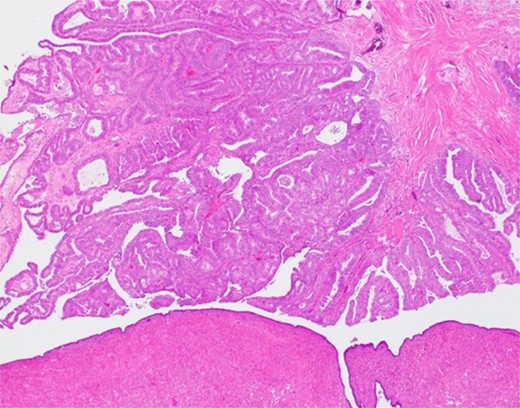

The histological findings with hematoxylin-eosin stain (H&E) revealed a cystic lesion with a very small and relatively dense stroma under the epithelium in the left paratubal region (Fig. 3). This stroma is CD10 positive in a small portion, suggesting the possibility of endometriosis (Fig. 4). Moreover, adenocarcinoma is arises from this cyst (Figs 5 and 6). There was no disseminated lesion in bilateral adnexa and uterus.

With these histological findings, we diagnosed the tumor as an endometrioid carcinoma arising from the paraovarian cyst.